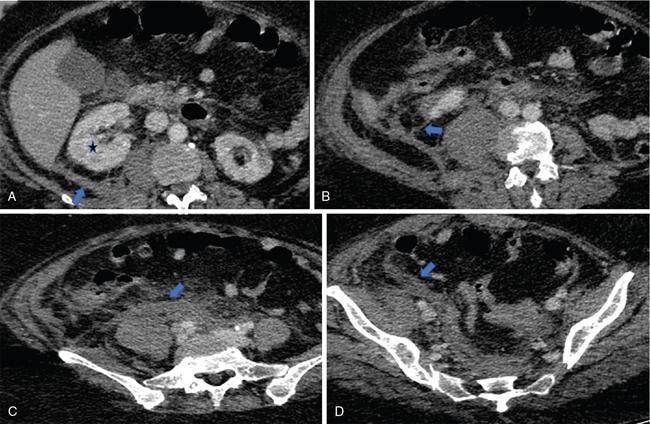

Fig. 10.17.1.3 Contrast-enhanced axial CT sections in a case of acute pancreatitis (asterisk in A); the pancreas appears diffusely bulky with peripancreatic fat stranding. Thickening of the anterior renal fascia (blue arrows in B and C) with fluid collection in the anterior pararenal space (blue arrow in D).